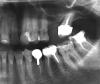

Несмеяна Опубликовано 3 февраля, 2010 Поделиться Опубликовано 3 февраля, 2010 Здравствуйте, уважаемые доктора. Буду признательна, если поможете мне в решении некоторых вопросов.По первому снимку:1) Верхняя пятерка и семерка слева слегка подвижны, имеют клиновидный дефект. Врач рекоменовал 5 - умертвить и сделать мост (5 и 7 под опору). Мотивируя тем, что мост укрепит 5 и 7 зуб - и уменьшит нагрузку. Ну и 3 дня назад удалил нерв из 5 зуба и запломбировал гуттаперчей.Позавчера порывшись в интернете обнаружила, что не следует делать мосты на подвижных зубах и мост только усилит нагрузку на них. 5 - жалко, но ничего не попишешь,дело сделано.Имплант пока поставить не могу, т.к. он подразумевает синус -лифтинг, а это все вместе дорого, а у меня по плану и так расходы на зубы грядут великие, в т.ч. имплантация зуба в нижнем ряду.Можно ли эти 2 зуба посадить под коронку и нужно ли делать вкладку? Стоит ли тянуть с имплантацией ( не рассосется ли кость совсем?) или дождаться пока пошатывающиеся зубы наконец выпадут, а потом сделать синус-лифтинг и пару имплантов?Посоветуйте, что мне с ними делать? 2) Можно ли поставить коронку на нижнюю шестерку в том состоянии как есть, или надо перелечивать и вкладку ставить? По второму снимку: 1) Можно ли на верхней шестерке (зуб резорциненный, не беспокоит более 15 лет) поменять коронку без прохождения каналов?2) Нужно ли на 2 верхний справа одевать коронку или можно закрыть его виниром?Он мертвый. Если коронку, то какую, чтобы не почернела у десны? И еще вопрос, не знаю только к трапевтам или к ортопедам, Эмаль передних зубов сильно стирается изнутри, зубы нарощены, но чувствительность на холод сильная. Что лучше в данном случае - коронки или виниры, и можно ли вообще винирами закрыть внутреннюю сторону зуба? Жалко их умертвлять подкоронки... Спасибо. Извините, что так много вопросов. Ссылка на комментарий

Sir Edward'S Опубликовано 6 февраля, 2010 Поделиться Опубликовано 6 февраля, 2010 Здравствуйте, уважаемые доктора. Буду признательна, если поможете мне в решении некоторых вопросов.По первому снимку:1) Верхняя пятерка и семерка слева слегка подвижны, имеют клиновидный дефект. Врач рекоменовал 5 - умертвить и сделать мост (5 и 7 под опору). Мотивируя тем, что мост укрепит 5 и 7 зуб - и уменьшит нагрузку. Ну и 3 дня назад удалил нерв из 5 зуба и запломбировал гуттаперчей.Позавчера порывшись в интернете обнаружила, что не следует делать мосты на подвижных зубах и мост только усилит нагрузку на них. 5 - жалко, но ничего не попишешь,дело сделано.Имплант пока поставить не могу, т.к. он подразумевает синус -лифтинг, а это все вместе дорого, а у меня по плану и так расходы на зубы грядут великие, в т.ч. имплантация зуба в нижнем ряду.Можно ли эти 2 зуба посадить под коронку и нужно ли делать вкладку? Стоит ли тянуть с имплантацией ( не рассосется ли кость совсем?) или дождаться пока пошатывающиеся зубы наконец выпадут, а потом сделать синус-лифтинг и пару имплантов?Посоветуйте, что мне с ними делать? 2) Можно ли поставить коронку на нижнюю шестерку в том состоянии как есть, или надо перелечивать и вкладку ставить? По второму снимку: 1) Можно ли на верхней шестерке (зуб резорциненный, не беспокоит более 15 лет) поменять коронку без прохождения каналов?2) Нужно ли на 2 верхний справа одевать коронку или можно закрыть его виниром?Он мертвый. Если коронку, то какую, чтобы не почернела у десны? И еще вопрос, не знаю только к трапевтам или к ортопедам, Эмаль передних зубов сильно стирается изнутри, зубы нарощены, но чувствительность на холод сильная. Что лучше в данном случае - коронки или виниры, и можно ли вообще винирами закрыть внутреннюю сторону зуба? Жалко их умертвлять подкоронки... 1) чем дольше вы откладываете с удалением и имплантацией тем меньше останется костной тканитам уже имеется воспалительный процессмостовидный протез не стоит делать .он еще больше нагрузит подвижные зубы.лучше удалить и сделать сьемный протез с целью сохранения ваших передних зубов.2) конечно можно сделать все,но лучше перелечить зуб(каналы не запломбированы)изготовить культевую вкладку и покрыть зуб коронкой.коронку любую на ваш выбор.с передними зубами нужно заниматься только после решения всех проблем с жевательными зубами.можно закрыть винирами и сохранить их живыми Ссылка на комментарий